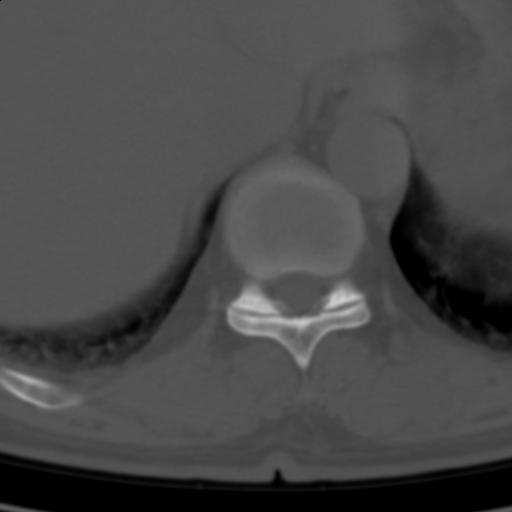

标题: CT25189:胸椎ct,请会诊!

既往食管癌,现行ct检查!

仅见椎体退行性改变

中上段食道癌,椎体轻度退变。

椎体退行性改变,食管癌。

支持中上段食道癌,椎体轻度退变,必要时做ect。

支持中上段食道癌,椎体轻度退变。